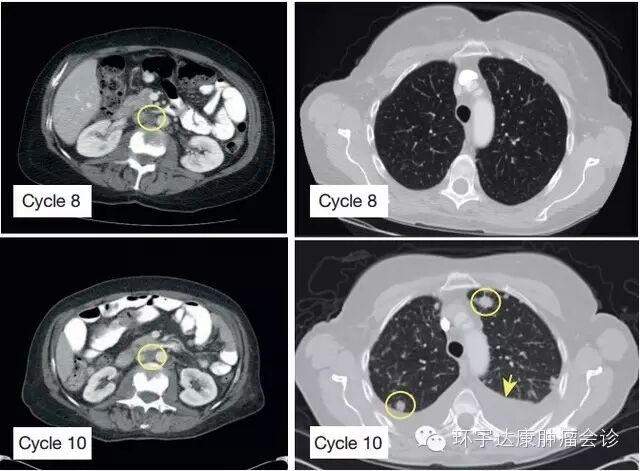

图 1. 指定患者予 BYL719 治疗后的临床反应 CT 扫描显示稳定(反应),完成第十周期的 BYL719 治疗后出现主动脉旁淋巴结转移(黄色圈、左列)和肺部新的病灶(黄色圈、右列),箭头所示为胸膜渗出

此发现使其入组一项Ⅰ期临床试验,检测抗肿瘤药物 BYL719 的毒性和耐受性(NCT01219699)。根据 RECIST 1.0 标准,患者迅速获得部分缓解,并持续 9.5 月(表 1 和扩展数据 图 1)。基于此,多个部位的肿瘤包括大动脉旁淋巴结是稳定的,而肺部肿瘤出现进展(图 1),终止 BYL719 的治疗。 患者的临床状态迅速恶化,停止 BYL719 治疗 2 个月后死亡。他们很快对患者进行了解剖并对 14 个转移灶上取得的材料进行收集和测序。